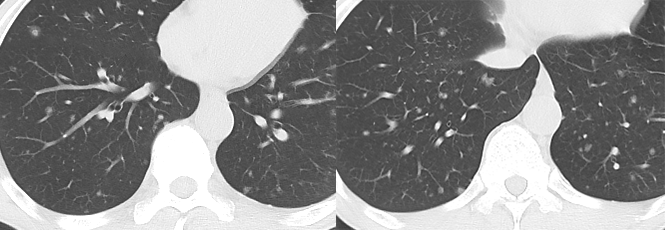

空洞性肺转移瘤

文献报道空洞型肺转移主要来自鳞癌和腺癌,鳞癌占 1/2 ~ 2/3,主要来自男性头颈部与女性生殖器肿瘤,其余为腺癌,主要来自结肠与乳腺癌。单亦有研究认为空洞性转移主要来自腺癌。其产生机制可能与鳞癌中心角化物排空、腺癌黏液样退变后黏液排空、肿瘤血供不足引起坏死、肿瘤继发脓肿、化疗、阻塞性肺气肿等有关。空洞性肺转移瘤变化快,短期内可见肿瘤增大、增多。CT 上空洞型转移结节外形上多保持了转移瘤的基本特点,即多发、圆形、边缘光整。洞壁多薄而均匀,内外壁光整,直径多 < 1.0 cm,部分洞壁厚薄不均,厚壁空洞病变可随着病灶增大而出现分叶、毛刺及壁结节等恶性空洞特点,部分空洞型肺转移洞壁可菲薄(称空泡更合适)。

乳腺癌空洞性肺转移。

54 岁男性,肾癌病史。左肺下叶厚壁空洞性转移(穿刺证实),左肺另见不伴空洞的实性小结节转移灶。

男,63 岁。食管鳞癌术后 3 年,痰中带血丝半年。穿刺证实双肺多发空洞和空泡转移,周围磨玻璃密度是转移瘤引起出血。